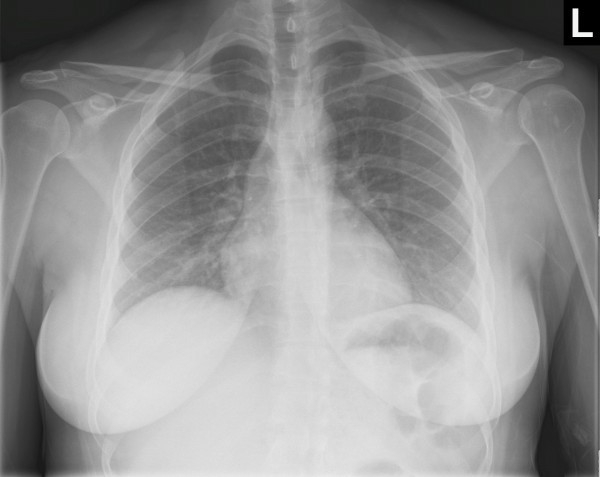

Thoracic Injuries: From Conventional X-Ray To Multidetector CT

Spectrum of lesions to be assessed in thoracic trauma Have great medical importance, social and (aortic injury) Multiple rib fractures (flail rib, CLASSIFICATION OF ... Fetch Document